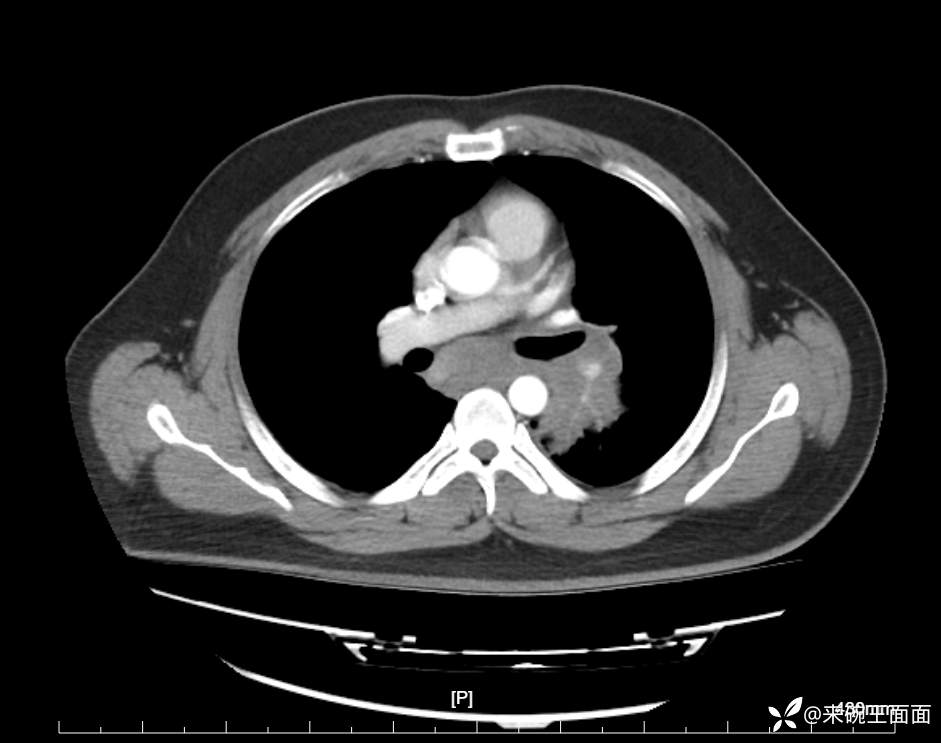

性别:男

年龄:27岁

主诉:胸闷胸痛数月余,休息后可自行缓解,无咯血症状。

个人史:数年吸烟史,具体不详。